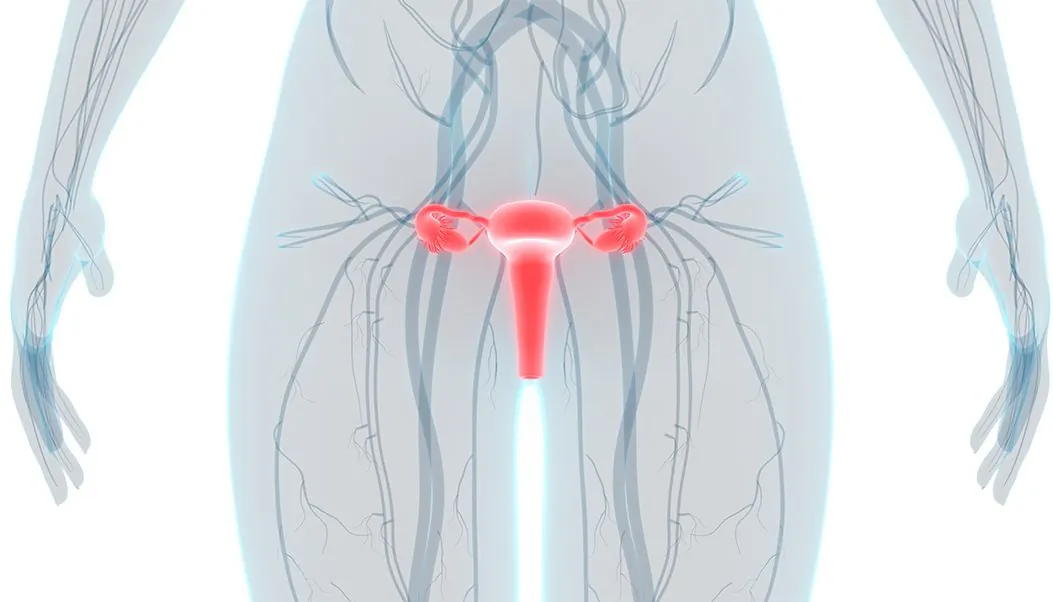

Gynecologic cancers include all cancers of the female reproductive system, such as cancers of the cervix, ovaries, fallopian tubes, uterus, vulva, and vagina. In the United States, it is predicted that over 100,000 women will be diagnosed with gynecologic cancer in 2018 alone. Over 30,000 women are predicted to die from this group of cancers.